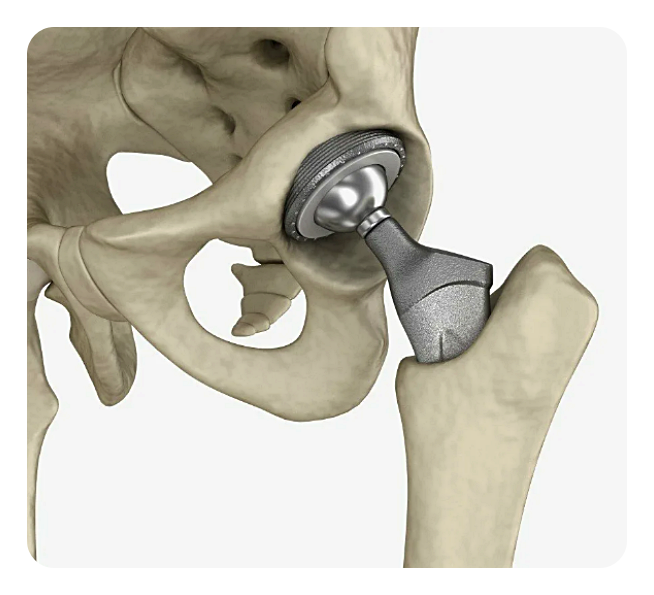

인공관절 치환술: 이 수술은 손상된 관절을 제거하고 그 자리에 인공 관절을 넣는 방식으로 이루어집니다. 인공관절은 대체로 금속, 플라스틱, 혹은 세라믹으로 만들어집니다.

특징: 인공관절 수술은 기본적으로 손상된 고관절을 제거하고 그 자리에 인공관절을 삽입하는 수술입니다. 이 인공관절은 금속, 플라스틱, 혹은 세라믹 등의 재료로 만들어져 있습니다.